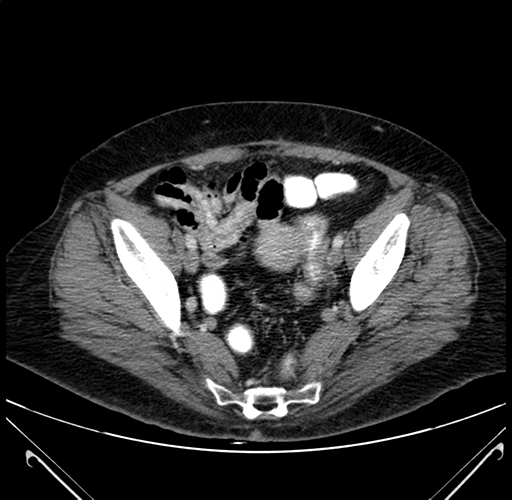

Pre-Chemo: Axial Venous